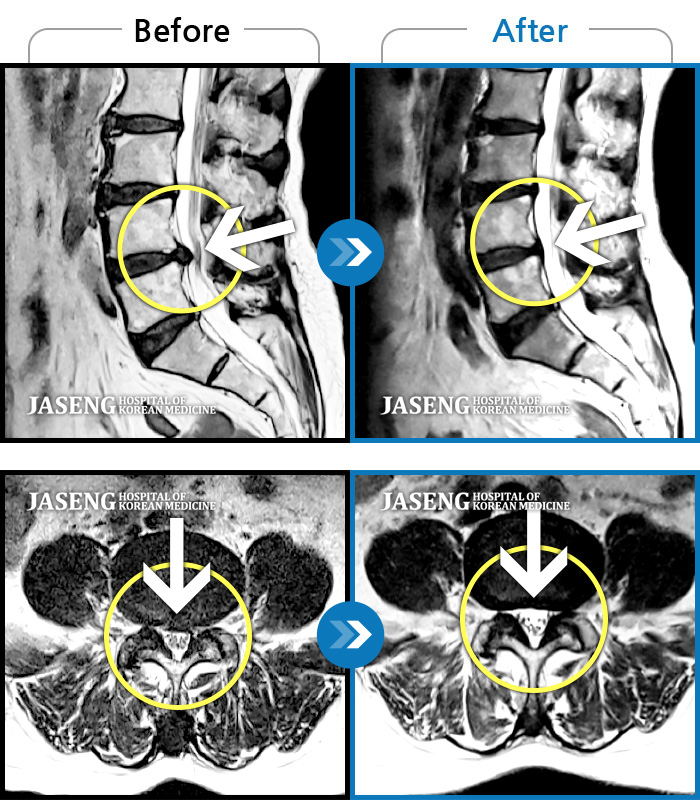

처음엔 이곳저곳 아파서 확실하게 어디가 아팠는지 몰랐는데 사고 후 일주일쯤 될 무렵 MRI촬영후 정확하게 진단을 받았습니다

허리디스크 2단계(초기) 진단을 받긴 했으나 다행히 근육량이 많아 모르고 살았는데 사고로 인해 디스크에 상처가 생겨 힘든 나날을 보내고 있습니다

70대 어머니가 디스크파열로 수술을 당장해야한다는 큰병원의 권유를 뒤로하고 자생을 결정하고 엄봉군원장님을 만났습니다. 두달여 치료받고 많이 호전되었고 갈때마다 진심을 다하시는 원장님으로 인해 정서적인 치료도 받고 있답니다 앞으로도 잘 부탁드립니가!!

디스크수술만 두번했어요 사고때문에 생긴 통증때문에 걱정이 많았어요 엄원장님 설명도 알기쉽게 해주시고 환자에대한 배려가 참 많은 분이셔서 많은 도움을 받고있습니다 적절한 치료처방으로 상태도 많이 호전되어 더 신뢰가가고 너무 감사해요 이렇게남아 감사의 글을 드립니다